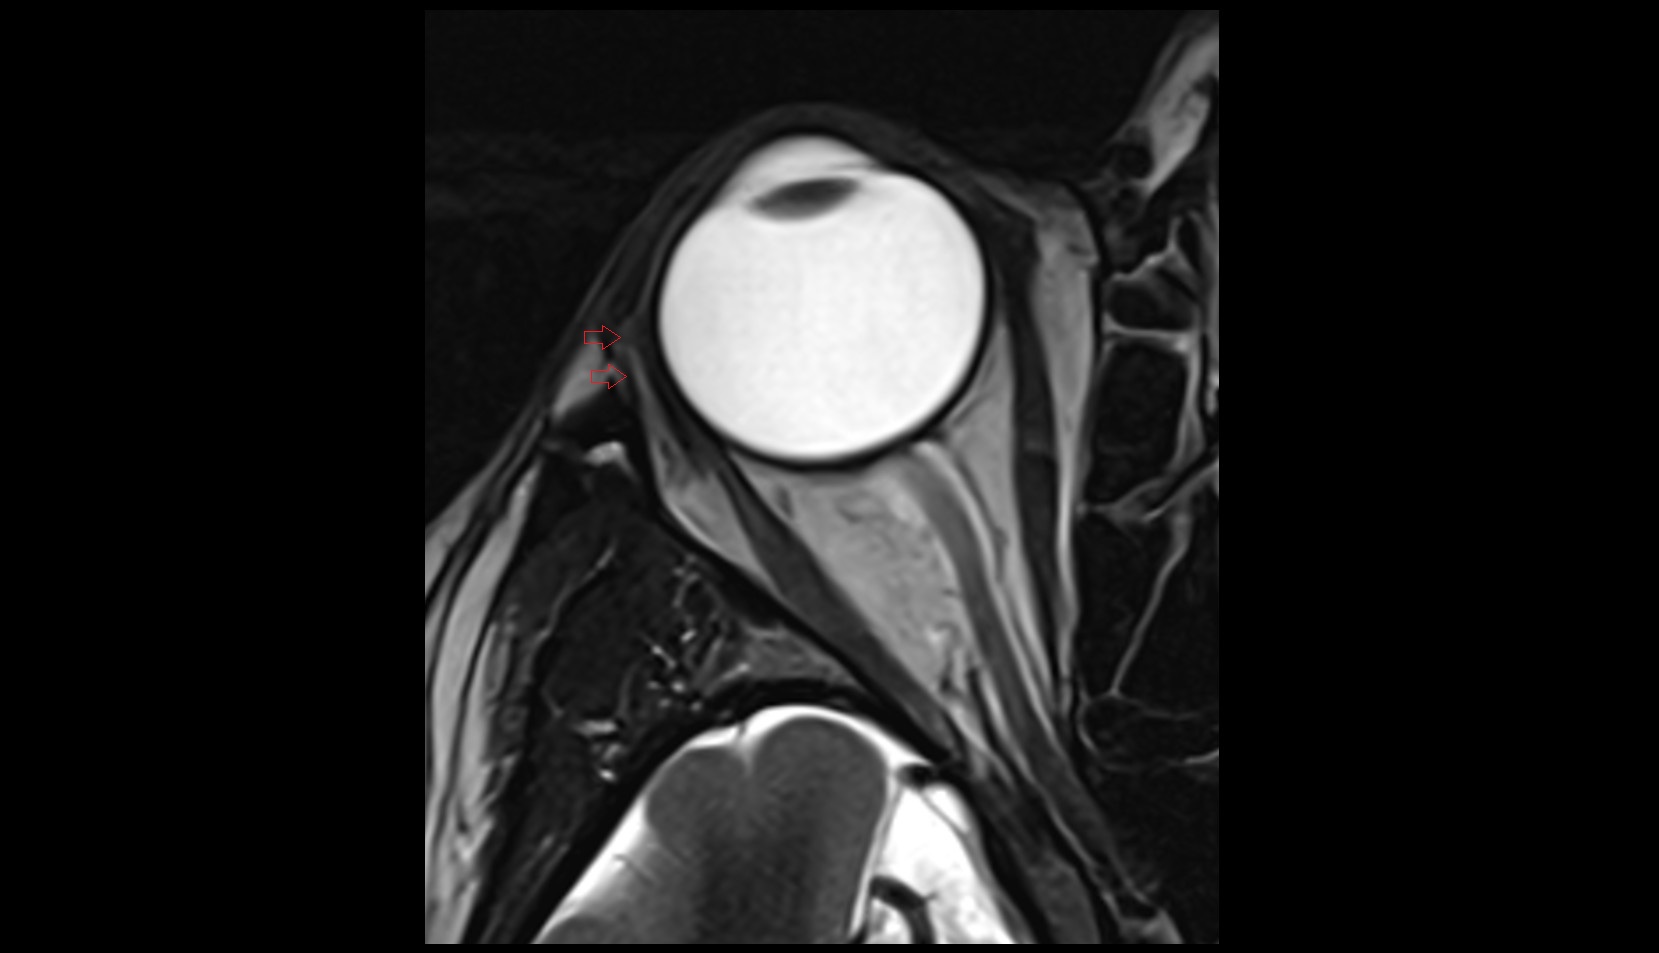

- Temporomandibular joint

- Mandibular condyle

- Mandibular fossa

- Articular disc of temporomandibular joint

- Articular eminence

- Superior head of lateral pterygoid muscle

- Inferior head of lateral pterygoid muscle